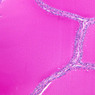

The thyroid gland (slide B-51, lead hematoxylin [10x, 20x, 40x, 40x]; B-52, H&E [10x-labeled, 20x, 40x-labeled, 40x]; B-53, PAS [2.5x, 10x, 20x, 40x]) consists of many closely packed, roughly spherical structures known as follicles, which are enclosed in a thick connective tissue capsule. Connective tissue septa extend from the capsule into the substance of the gland, carrying numerous blood vessels. Follicular cells are arranged as shells of simple cuboidal epithelium surrounding a gelatinous mass known as colloid. Look for a ring of epithelial cells around the homogeneous, pink-staining colloid. The cytoplasm of the follicular cells (principal cells) is faintly basophilic. The follicular cells secrete thyroglobulin, a glycoprotein, which is stored extracellularly in the colloid. In response to TSH, the follicular cells endocytose the colloid and hydrolyze it to form thyroxine. You can see where colloid has been resorbed because this process leaves small holes in the colloid adjacent to the follicular cells. These holes are known as resorption lacunae (B-52 [10x, 20x, 40xlabeled]). Very active follicles may exhibit a columnar epithelium and increased numbers of resorption lacunae. Between follicles, the stroma of the thyroid gland consists of a thin layer of connective tissue and a rich capillary network. Parafollicular cells (light cells or C cells) are located in the connective tissue between follicles or adjacent to follicular cells within follicles. When they lie within the follicular wall, the parafollicular cells do not reach the lumen. Parafollicular cells are slightly larger than the follicular cells and, in H & E preparations, have a more lightly stained cytoplasm (B-52, H&E [10x, 20x, 40x-labeled] [10x-labeled, 20x, 40x-labeled] [10x, 20x, 40x] [10x, 20x, 40x]; B-53, PAS [10x, 20x, 40x]). Parafollicular cells are readily identifiable in slide B-51 (stained with lead hematoxylin), where they appear as purplish-black structures in which the nuclei are difficult to discern (B-51 [10x, 20x, 40x-labeled]). These cells secrete calcitonin, which lowers serum calcium levels by inhibiting bone resorption and accelerating osteoid calcification.